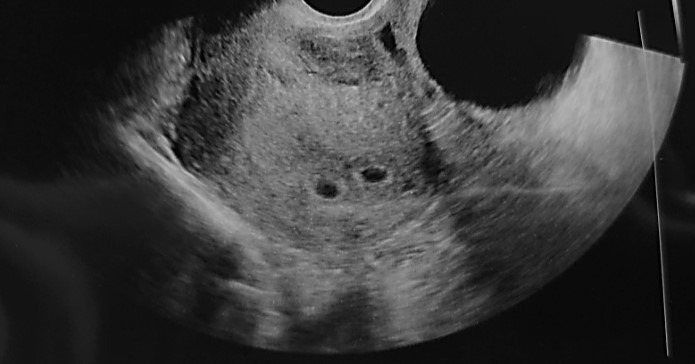

피검사 수치가 평균 산모 수치보다 2배 이상 높게 나와서 혹시나 했는데 역시나 쌍둥이라고 했다. 두 개의 아기집도 만들어지고 있다고 했다. 지금껏 보아왔던 초음파 사진과는 다른 두 생명체가 자리 잡은 두 개의 아기집이었다. 한 번에 두 생명을 얻게 되다니... 순간 두려움도 들었지만 내 입꼬리는 저절로 올라가고 있었다. 호기롭게 시작했던 임신 시도, 두 번의 실패 후 찾아온 콩알만 한 두 명의 생명체 보니 그동안 고단했던 몸과 마음이 사르륵 녹아내리는 것 같았다.

p1_1.jpg